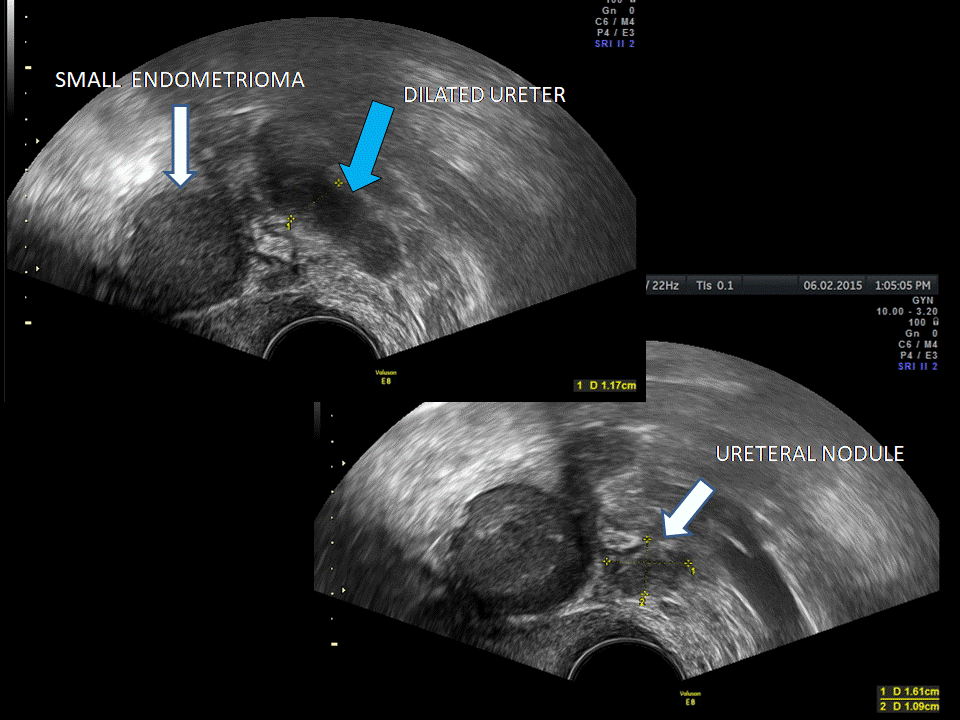

from www.volusonclub.net

Using Transvaginal Ultrasound for Ureteral Endometriosis Empowered

Using Transvaginal Ultrasound for Ureteral Endometriosis Empowered Pelvic Exam For Endometriosis If you have symptoms, call your gynecologist. A pelvic exam generally lasts a few minutes in length, and is a comprehensive evaluation of your reproductive system. Offer an abdominal and pelvic examination to women with suspected endometriosis to identify abdominal masses. Effective management of endometriosis requires prompt diagnosis to enable early multidisciplinary intervention that aligns with patient needs and priorities.. Pelvic Exam For Endometriosis.